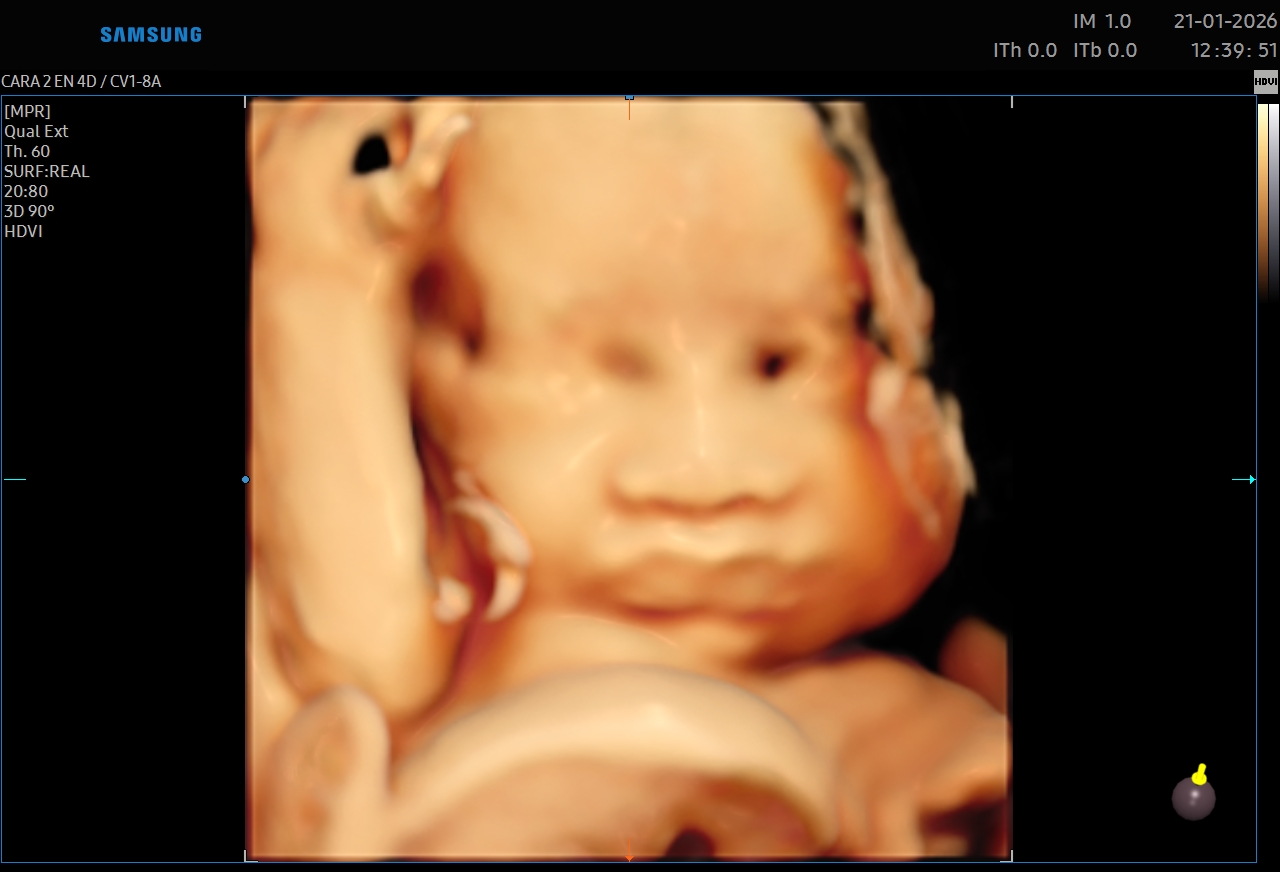

Ecografías 5D

La ecografía 5D es una experiencia única que te permite ver a tu bebé con un nivel de realismo sorprendente, capturando detalles como sus gestos, expresiones y movimientos en tiempo real.

Gracias a esta tecnología avanzada, podrás observar el rostro de tu bebé con mayor claridad, creando un vínculo emocional aún más especial antes de su nacimiento. Es el momento perfecto para compartir con tu familia y guardar recuerdos inolvidables de esta etapa tan importante.

Además de ser una experiencia hermosa, este estudio se realiza con equipos de alta tecnología y bajo supervisión médica, garantizando seguridad tanto para la mamá como para el bebé.

1. El momento ideal es a partir de semana 26 hasta la 32